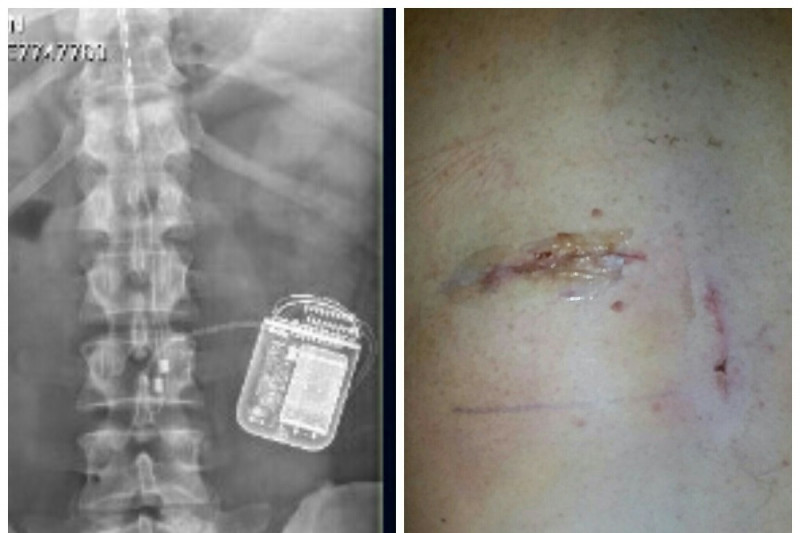

I was injured in August of 2015 during a drill weekend and my life has had some major changes. I suffered for about a year and half before doctors could give me a correct diagnosis (nerve damage). I then had surgery in February of 2017 to place a spinal cord stimulator in my back to try to help ease the pain level. The spinal cord stimulator (SCS) device was surgically placed under my skin (see photos) and it sends an electric current to my spinal cord. A small wire carries the current from a pulse generator to the nerve fibers of the spinal cord. When turned on, the SCS stimulates the nerves in the area where my pain is felt. I have to keep the device charged daily and I have went (and continue) through several changes in settings since having the device placed to try to find a comfortable setting for me to have enough comfort to function with limited capabilities. I deal with constant pain and discomfort in my back and legs on a daily basis. I have went from being a full-time, hard worker clocking in many long hours to not being able to do simple things like sitting for a long period or walking long distances. Even driving or riding to doctor's appointments cause me a lot of pain. I am constantly moving to try to find a comfortable position, I can not sit in a chair for very long, I need to adjust constantly to a laid back position with my feet up. I can not stand on my feet for very long either, I have to walk extremely slow when my back and leg are hurting. I am no longer able to work even part-time. I have no income coming in at all, my wife receives a very small portion (it is split 4 ways) of her Dad's pension from when he passed away. She is currently looking for work, with no luck so far. I received a letter from my mortgage company saying that I have until September 9th to be caught up with payments or I could lose my home. I currently owe $1,978.70, that is 3 months behind. I am also about to lose my car. I owe $825, it is also 3 months behind, to catch it up before they come and take it. I have used up all my resources that will help military people and I have emptied my saving's account. Creating this fundraiser is out of my comfort zone but my family comes before my pride. I am in a desperate situation which calls for desperate measures. I appreciate any help anyone can give at this time.